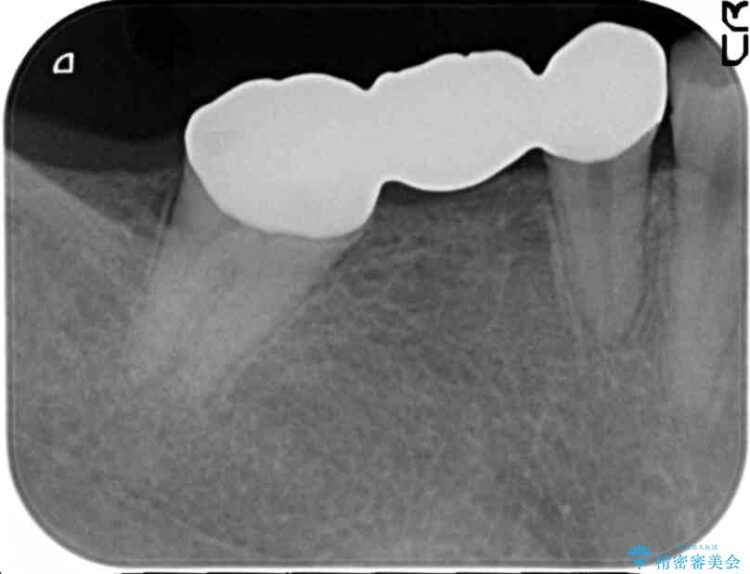

診査した結果、欠損した状態で長期間放置していたことが原因で最高峰の奥歯が欠けた部分に向かって傾斜してしまっていました。

この状態のままブリッジ治療へと進んでしまうと神経が露出する可能性が否定できないため、まずワイヤー装置による部分矯正で歯軸を通常位置へ戻してから補綴治療を行うこととしました。